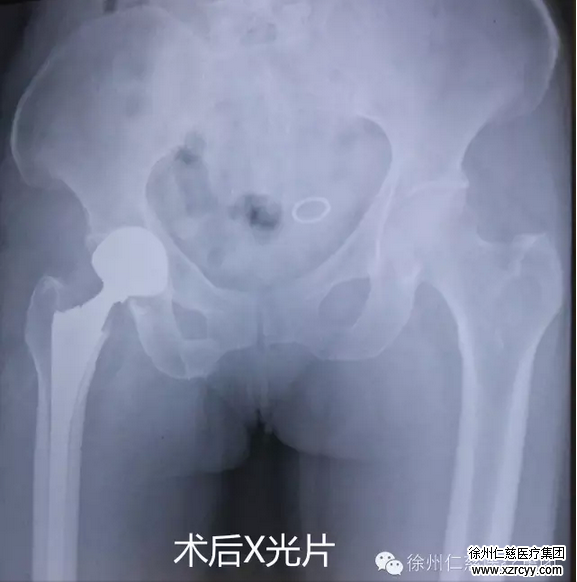

典型病例介紹

患者女,73歲,因摔傷致右側(cè)股骨頸骨折,在徐州仁慈醫(yī)院關(guān)節(jié)外科行右側(cè)SuperPath微創(chuàng)傷全髖關(guān)節(jié)置換術(shù),手術(shù)全程歷時(shí)1.5小時(shí)。手術(shù)過(guò)程不切斷任何肌肉或肌腱,完整保留了外旋肌群和關(guān)節(jié)囊。不必做任何活動(dòng)角度的限制,術(shù)后第一天患者即下床進(jìn)行了鍛煉,大大縮短了患者康復(fù)的時(shí)間,達(dá)到了真正意義上的微創(chuàng),實(shí)現(xiàn)了“快速康復(fù)”的理念。